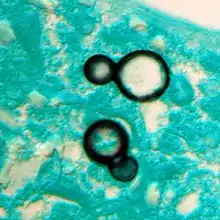

Once suspected, the diagnosis of blastomycosis can usually be confirmed by demonstration of the characteristic broad based budding organisms in sputum or tissues by KOH prep, cytology, or histology.[27] Tissue biopsy of skin or other organs may be required in order to diagnose extra-pulmonary disease. Blastomycosis is histologically associated with granulomatous nodules.

Granuloma with early suppuration. Fungal organisms difficult to recognize at this low magnification.

Large yeast-like fungi seen within giant cells at arrows.

Large yeast-like fungi seen within giant cells at arrows. Budding yeasts in cytoplasm of giant cells at arrows. Broad-based budding and double contoured cell wall seen in the giant cell in the center is characteristic of Blastomyces dermatitidis.